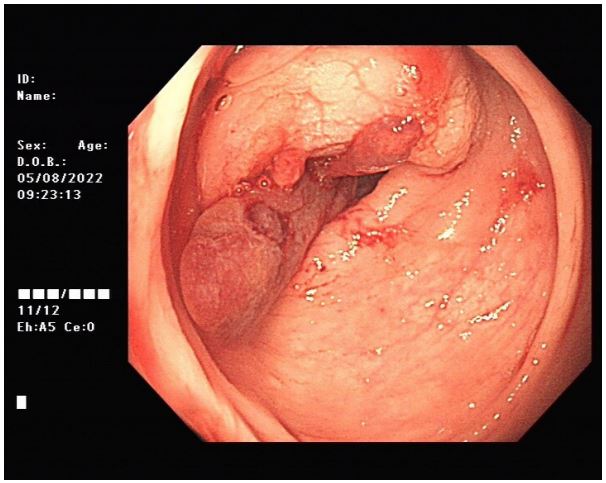

Colonic occupying lesion (whole abdomen enhanced CT is recommended). The intraoperative pictures are shown in Figure 2. Further CT examination suggested that: The intestinal wall at the junction of sigmoid colon and rectum was thickened with mass-like changes, the range was about 4.4 cm × 2.3 cm, the measured CT value was about 49HU, after enhancement, moderate enhancement was seen, the CT value was about 75HU, the plasma membrane surface of the intestinal canal corresponding to the lesion was still smooth; the distribution and morphology of the remaining abdominal intestinal canal did not show obvious abnormal changes, the mesenteric fat gap was still clear, and no obvious enlarged lymph nodes were seen. No obvious enlarged lymph nodes were seen. The bladder was full and no significant abnormal density foci were seen in the bladder. A small cystic hypodense foci, about 2.4 cm × 1.7 cm in size, could be seen in the right adnexal area, and no significant abnormal enhancement was seen after enhancement. The size and shape of the uterus were acceptable, and no significant abnormal enhancement was seen after enhancement. The biopsy report after colonoscopy suggested tubular adenoma (rectum) with mild heterogeneous hyperplasia of the glandular epithelium (low-grade intraepithelial neoplasia). The patient was referred to a general hospital for gastrointestinal surgery, where colon cancer was highly considered and a biopsy was performed, which showed tubular adenoma (rectum) with low-grade intraepithelial neoplasia. The patient refused further treatment and returned to the hospital 2 months later with no significant change in the symptoms of anal distention. After MTD discussion, colonoscopy was performed again with the patient’s informed consent, and the endoscopist was changed. The lesion was partially excised from the colon with adequate information, and endometriosis was considered in the intraoperative frozen section, and the excised tissue was shown in Figure 3. Immunohistochemical results: CK (AE1/AE3) (+), CK20 (-), CDX-2 (-),CD10 (+), ER (3+), PR (2+), WT-1 (+), p53 (~5%+), Ki67 (~10%+). All pathological images are shown in Figure 4. See Figures 9 and 10 for details. postoperative symptomatic treatment and recovery was good. Postoperative follow-up until the writing of this manuscript the patient was generally well with no significant discomfort.

Figure 2: First colonoscopy image.

With the development of intestinal endoscopic techniques, new advances have been made in the diagnosis of intestinal endometriosis. Since the site of colorectal endometriosis is the anterior rectal wall and the anterior lower border of the sigmoid colon, growing from the plasma membrane layer into the intestinal lumen, enteroscopic manifestations are mostly signs of submucosal or extra-mural masses, which may be normal on the mucosal surface, but may show congestion, edema and superficial ulcers, sometimes inflammatory polyps, occasionally dark purple hemorrhagic spots in the submucosal layer, eccentric mucosal wrinkles, aggregates in the invaded intestinal canal, and the presence of fibrosis in Jiang W et al. [53] described 15 patients with intestinal mucosal endometriosis, whose mucosal changes were mainly characterized by (1) replacement of the intestinal mucosal surface epithelium by endometrial glands, (2) mingling of intestinal mucosal glands with endometrial glands, and (3) mixing of endometrial glands with intestinal mucosal glands. The glands are surrounded by endometrial interrogative cells, and the interrogative mass is seen to have hemorrhagic and edematous changes. The endometrial glandular epithelial luminal margin may be mildly serrated and irregular, lined with a single layer of epithelium, with tall columnar cells with cigar-shaped growing nuclei, acidophilic cytoplasm, no cellular secretion, ciliated (tubal epithelium) metaplasia, and other metaplasia such as squamous metaplasia, or significantly dilated glandular lumen with flattened lining epithelium. However, some endoscopic presentations lack specificity, so some physicians choose to perform simultaneous biopsies at endoscopy for suspicious sites. Endoscopic biopsies often obtain tissue that only reflects chronic injury but may lack a basis for a definitive diagnosis of endometriosis lesions, so this may lead to misdiagnosis [47]. Kim et al. [54] reported a positive rate of colonoscopic biopsies of only 47.0% (8/17), but their study hypothesized that increasing the number of biopsies may help to improve the positive rate of biopsies. The superficial mucosa of endometriosis lesions has more obvious inflammatory manifestations, and in some cases cryptitis, crypt abscesses and other pathological manifestations similar to inflammatory bowel disease can be seen [53], thus having an impact on the interpretation of pathological findings. The colonoscopic presentation and biopsy pathology of endometriosis lesions can be indistinguishable from inflammatory bowel disease, ischemic bowel disease, or even colonic malignancy, which may lead to unnecessary surgical treatment. Studies have reported that immunohistochemistry (CK7, ER, CK20, and CDX2) can help improve the diagnosis in cases of diagnostic difficulties [55]. The patient underwent 3 colonoscopies, and although the endoscopists were different on all three occasions, the microscopic manifestations all showed raised intestinal mucosal lesions, and the microscopic manifestations all first considered intestinal malignancy, because the lesions invaded the muscular layer but did not reach the mucosal layer, so although the specificity of the endoscopic manifestations was not obvious compared with malignancy, and the pathological results of all 3 biopsies did not suggest endometriosis, they were all diagnosed as low-grade. This is consistent with reports suggesting some difficulties in pathological diagnosis.